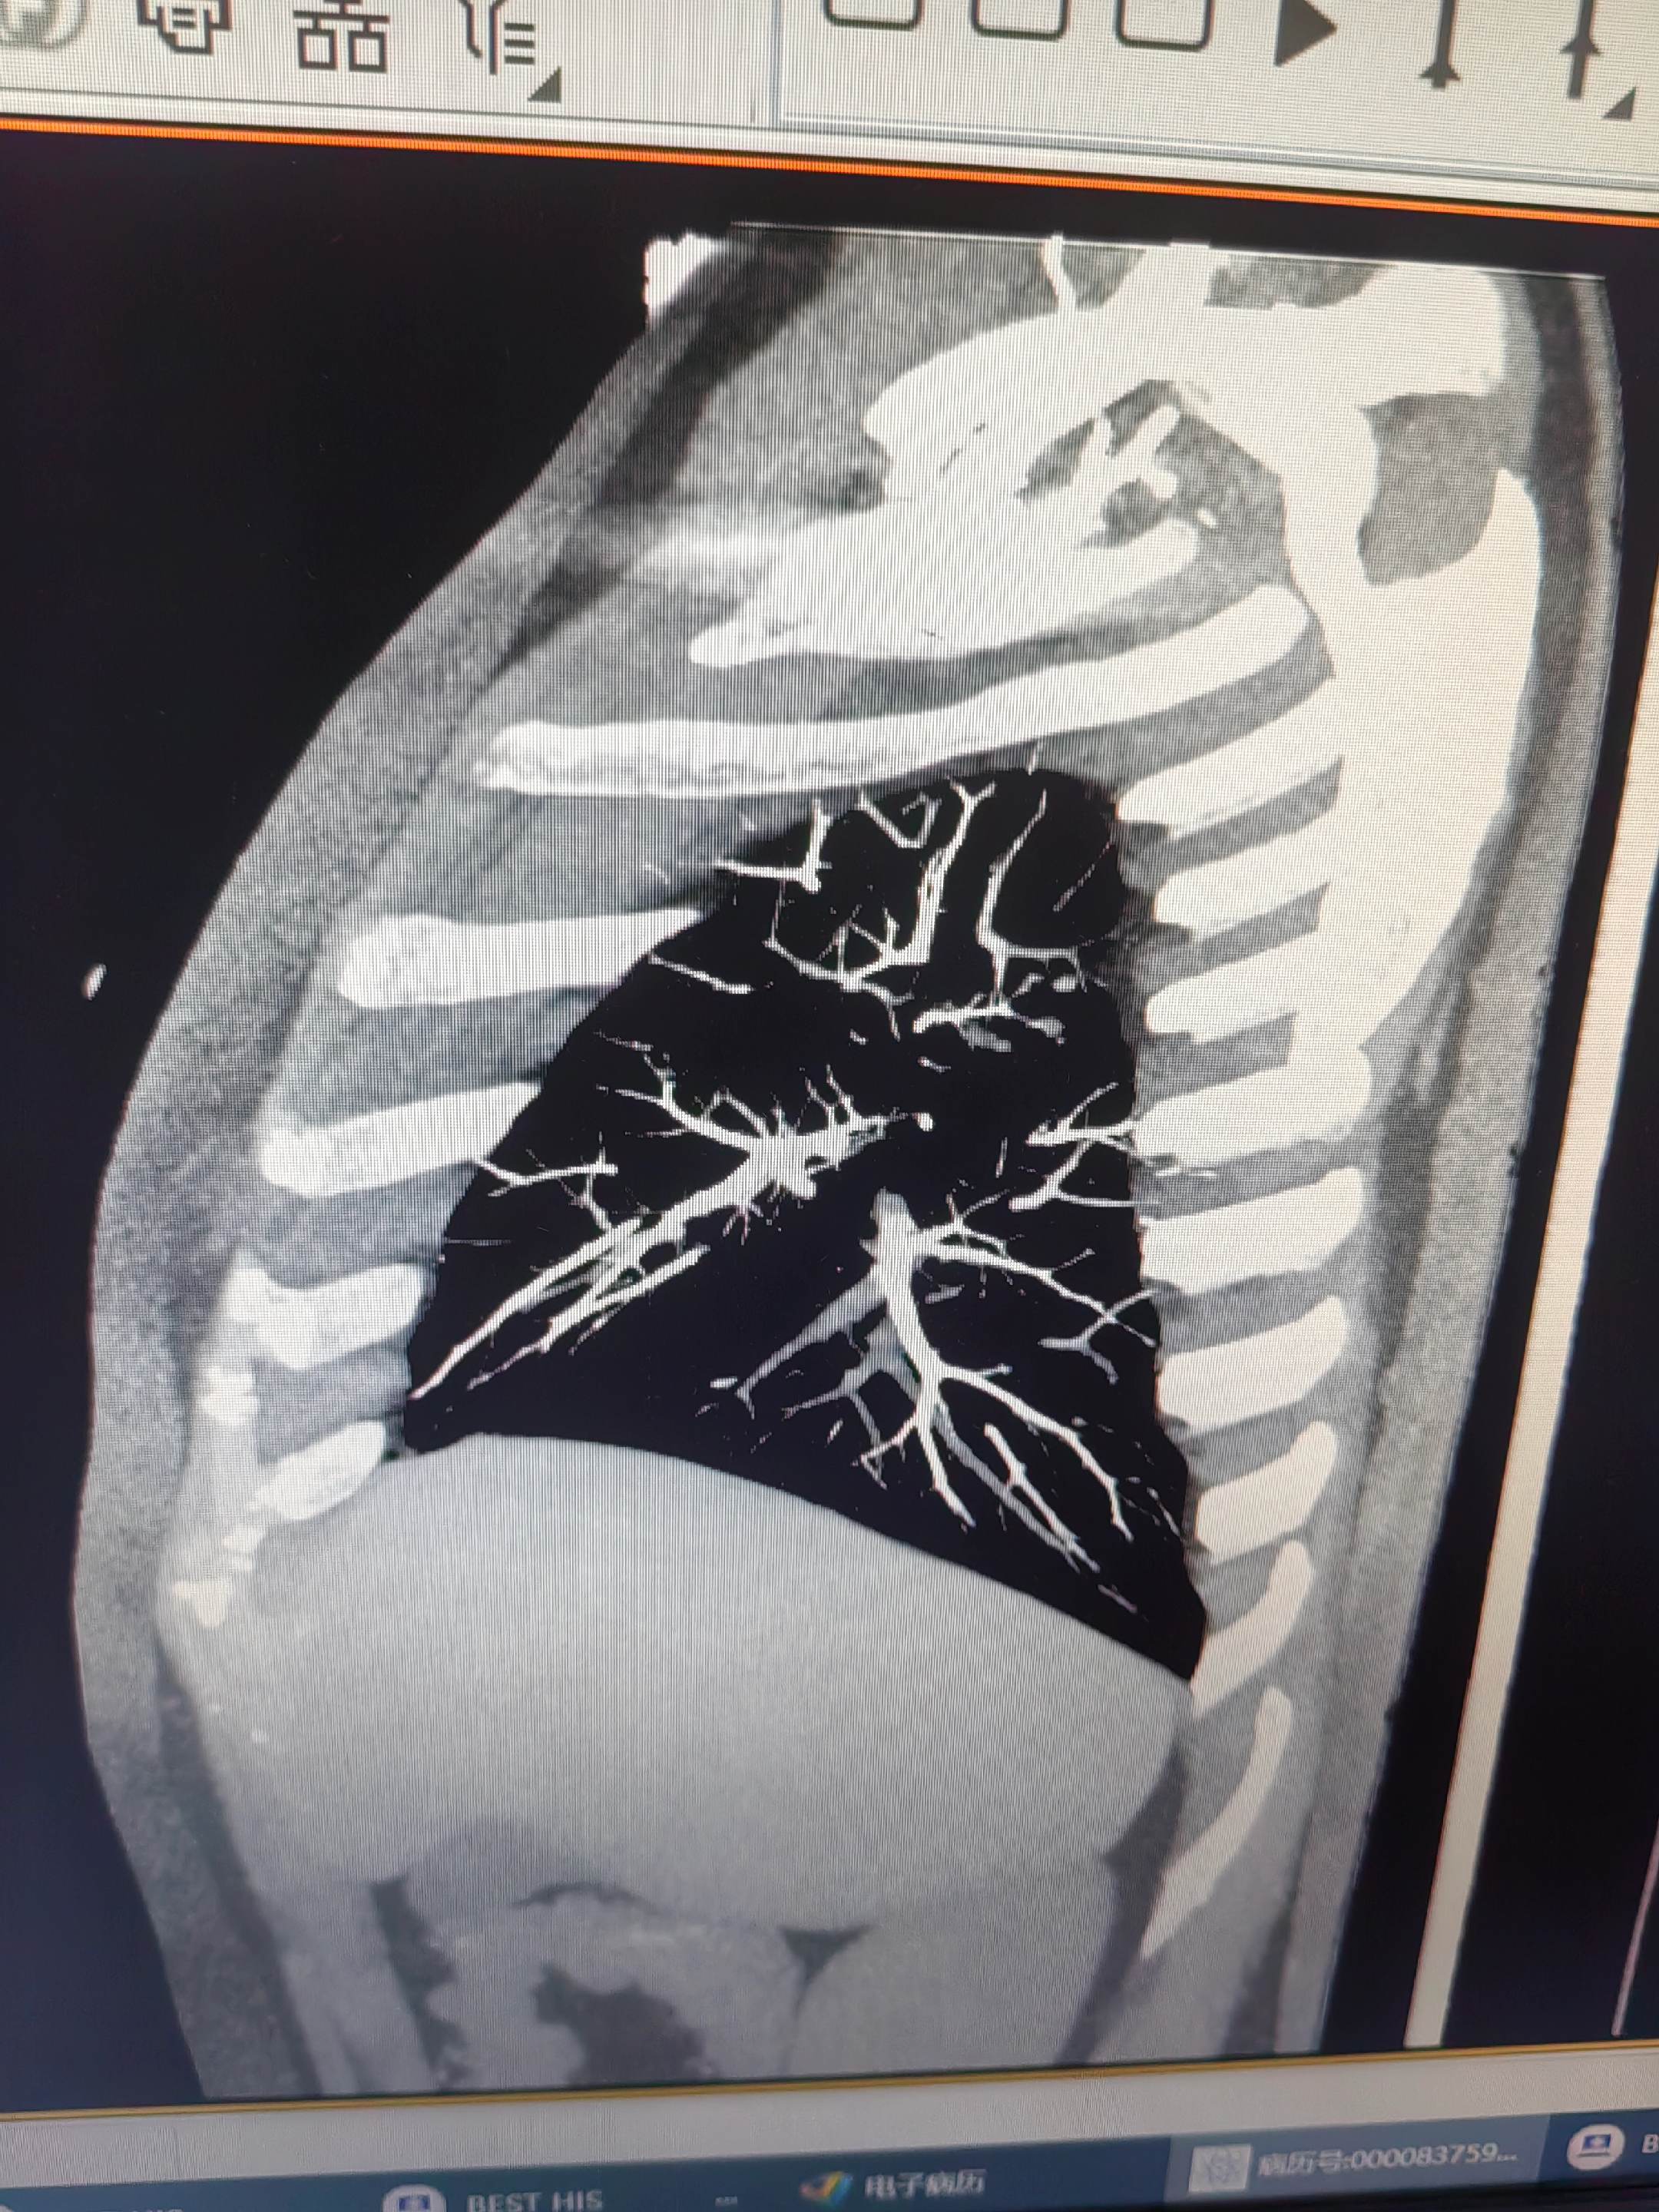

肺栓塞。